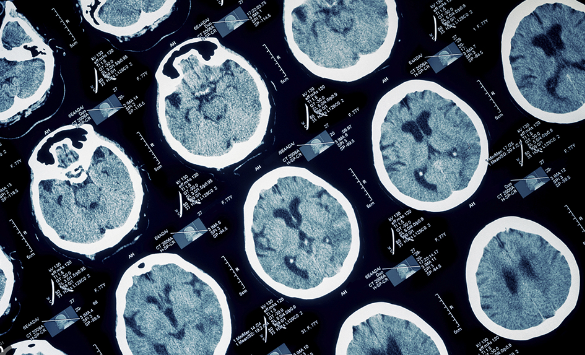

- 뇌 영상 검사: MRI 또는 CT 스캔을 통해 뇌의 구조적 변화를 확인